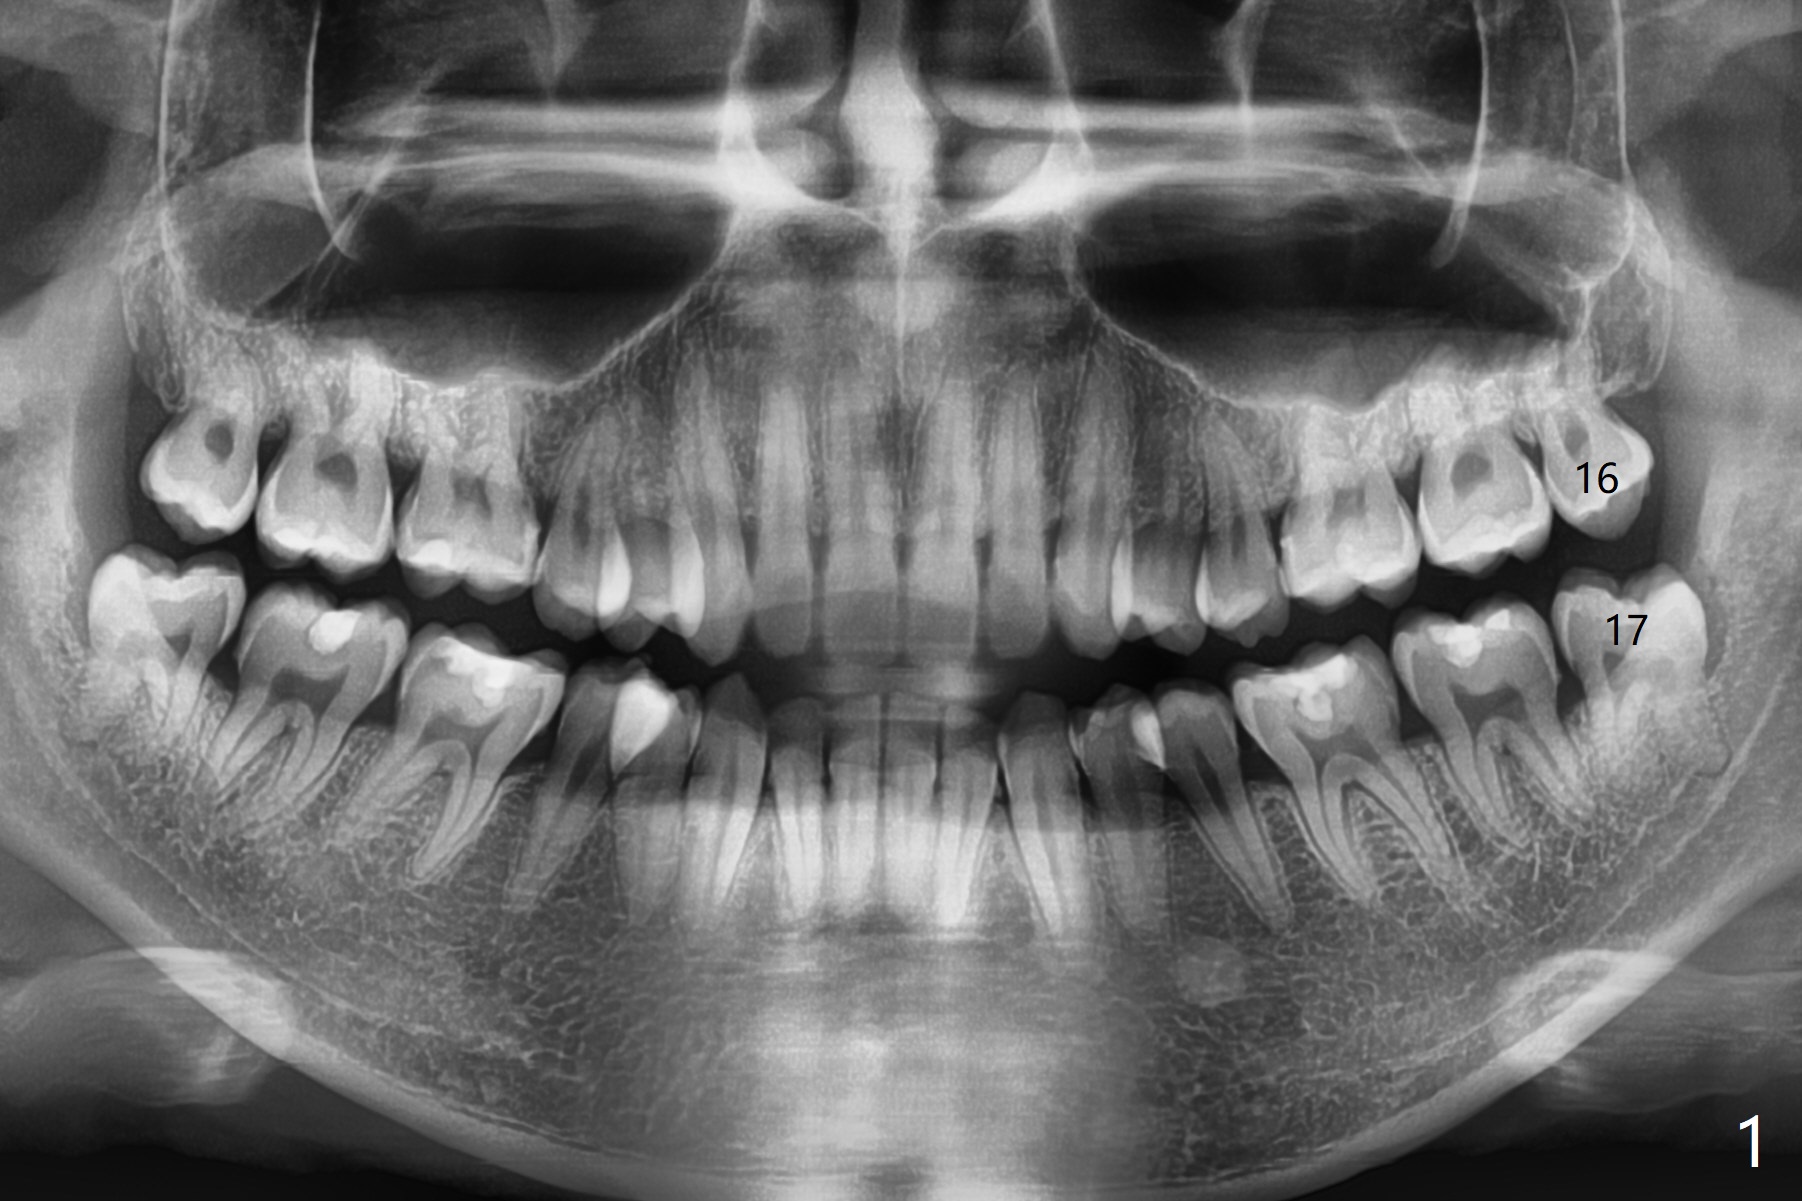

A 26-year-old man presents to clinic with pericoronitis at #17; the tooth #16 bites on the distal swollen gingiva of the tooth #17 (Fig.1). Since there appears to be no bone loss distal of #18, collagen plug, instead of Osteogen plug (Fig.2,3), will be placed in the socket(s) after extraction (Fig.4,5). For easy insertion, the plug is cut apically (Fig.6 *). The wound is closed with 4-0 plain gut suture. The patient returns for #1 and 32 extraction, eight months post #16 and 17 extraction. As usual, no bone substitute is placed in #1 socket after extraction (Fig.7). After #32 extraction, the distal socket looks large so that Augma (Bond Apatite) is placed and pressed (A), followed by a piece of Collagen Plug (C, to prevent Augma dissolved by saliva in case premature loss of suture). In fact there is also buccal defect at #32 due to chronic infection and heavy calculus. There is cortical bone formation at #16 socket opening (^). The mesial and distal sockets of #17 (*) seem to be obliterated because of placement of Collagen Plug. Return to Plug, Weichat Xin Wei, DDS, PhD, MS 1st edition 01/05/2019, last revision 09/22/2019